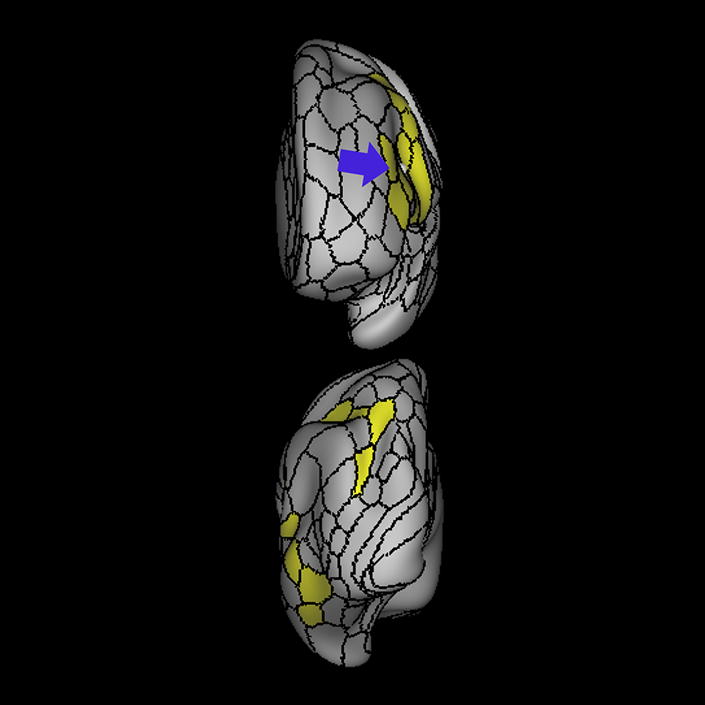

ᐅ SummaryArea 44: part of the inferior frontal gyrus of the lateral frontal lobe. Translates abstract and intentional information in the prefrontal cortex to more detailed representations to help guide the production of verbal and manual actions. In addition to its known association with Broca's area, is sometimes represented as part of Broca's complex ᐅ Where is it?Area 44 is at the posterior most part of the inferior frontal gyrus. It is the anterior bank of pars opercularis of the IFG. ᐅ What are its borders?Area 44 borders area 45 anteriorly and area 6r posteriorly. Area 8C is its medial border and its inferior border is wedged between then upper borders of Areas 6R and 6V. Its superior edge borders IFSp and IFJa. Its opercular surface is FOP4. ᐅ What are its functional connections?Area 44 demonstrates functional connectivity to areas SFL, IFSp, IFJa, 45, 47s, 47L, 9a, 9m, 8AV, 8BL and 8C in the dorsolateral frontal lobe, area 8BM in the medial frontal lobe, area 55b in the premotor areas, areas FOP5, AVI and PSL in the insula- opercular region, areas TGd, STSdp and STSvp in the temporal lobe, areas PFm, and PGi in the inferior parietal lobe, and no areas in the medial parietal lobe. ᐅ What are its white matter connections?Area 44 is structurally connected to the arcuate/SLF and the FAT. Connections with the arcuate/SLF project posteriorly and wrap around the Sylvian fissure to the middle temporal gyrus to end at TE1a and TE1m. There are also projections from the arcuate/SLF before it terminates to parcellations A5 and STSdp. The majority of the inferior connections of the frontal aslant tract end at 44, the tract is connected superiorly to superior frontal gyrus parcellations SFL, 6ma and s6-8. Local short association bundles are connected with 45 and 8C. White matter tracts from 44 in the right hemisphere have less consistent connections with the arcuate/SLF. ᐅ What is known about its function?Area 44 translates abstract and intentional information in the prefrontal cortex to more detailed representations to help guide the production of verbal and manual actions. Area 44, in addition to its known association with Broca's area, is sometimes represented as part of "Broca's complex", including Brodmann Areas 45, 46, 47 and the mesial supplementary motor area of 6, which contribute to a frontal-subcortical circuit. The right pars opercularis has also been implicated in cognitive inhibition in the overall context of working memory. |

A: lateral-medial

B: anterior-posterior

C: superior-inferior

DTI image |